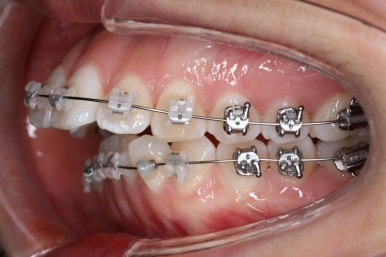

다시 이번 환자분으로 돌아가, 입 안모습을 보시겠습니다.

부산무턱교정 키다리아저씨치과에서 처음 내원하셨을 당시의 입 안의 모습입니다.

아래턱이 작아서 상대적으로 윗니들이 많이 돌출되었고, 뻐드러져 있습니다. 윗니들이 배열되어 있는 형태도 V자에 가깝게 입천장이 좁은 양상입니다.

장치를 부착하였습니다.

이번에 부착한 장치는 엠파워 클리어라고 하는 자가결찰 세라믹장치 입니다.

세라믹이기 때문에 덜 보이며 자가결찰 장치이기 때문에 초기에 가지런해지는 속도가 빠르고 통증이 덜한 장점이 있습니다.